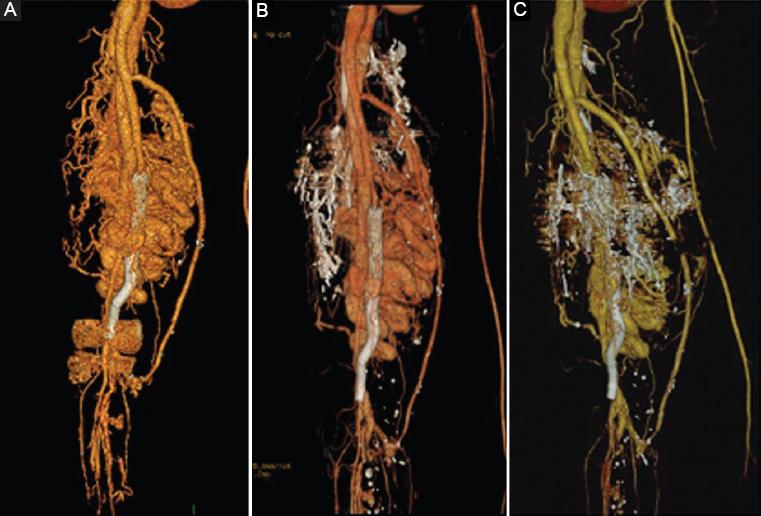

The CTA findings were then confirmed in the first endovascular session with the angiography, which also detailed multiple feeding vessels from the profunda femoris and superficial femoral artery. AVM was classified as a type IIIb according to the angiographic classification4, with multiple shunts between arterioles and venules and dilation of the fistulae. In the first endovascular intervention, feeding arteries embolization was made through a cross-over arterial left femoral access with selective catheter placement in the feeding vessels and then five Onyx-34 embolizations were made, final arteriography showed presence of multiple arteriovenous fistulae (Fig. 2A). In the second session, the left femoral puncture was done and a cross-over was made again with selective embolization with Onyx-34 of the hypogastric feeding vessels and selective embolization of right common femoral feeding vessels was done and five coils were used (Fig. 2B). In the third session, a direct puncture in the right femoral artery, then a selective feeding arteries embolization with Onyx-34 and eleven coils to the common and superficial femoral feeding vessels was done (Fig. 3A), together with direct US-guided puncture of the venous dilated veins. In the fourth and fifth sessions, an embolization with Onyx-34 and six coils both to superficial femoral feeding vessels and dilated superficial veins was done (Figs. 3B and C).

Figure 3 Third to sixth endovascular sessions. A: in the third session, a direct puncture in the right femoral artery, then a selective afferences embolization with Onyx-34 and eleven coils. B-C: in the fourth and fifth sessions, an embolization with Onyx-34 and six coils. D: after open surgery attempt, a final session was planned with selective catheter placement in the profunda femoris and embolization of afferences with Onyx-34 and 2 coils, the last arteriography showed significant decrease in fistulous shunts.

Open surgery was attempted for resection of accessible arteriovenous fistulae at the femoral bifurcation, fistulas between the femoral artery and vein were ligated and a selective arteriography was made clamping the superficial femoral and the profunda in different times, finding that all the remaining fistulous vessels were coming from the profunda femoris (Fig. 4). A final session was planned with selective catheter placement in the profunda femoris and embolization of feeding arteries with Onyx-34 and 2 coils, the last arteriography showed significant decrease in fistulous shunts (Fig. 3D). There were no complications documented in any of the sessions, and the patient was discharged in 24-48 h every time.

Figure 5 shows the evolution of the medial malleolus ulcer after the endovascular treatment and figure 6 shows the CTA 3D-vascular reconstructions evolution after treatment. Nowadays, the patient has minimal symptoms, with significant improvement in pain, with improved function and similar thigh diameter and the ulcer is significantly diminished in diameter as shown below.